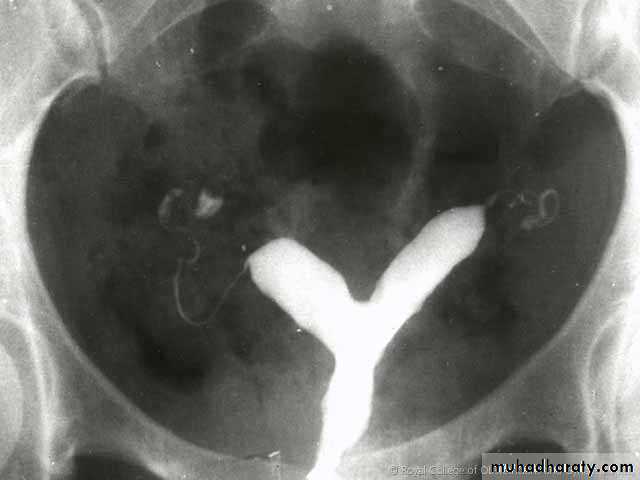

This is U/S of a patient presented with oligomenorrhea and infertility.

1. What is this gynecoiogical problem?2. List 3 other possible clinical presentation of this condition?

3. List 2 main hormonal changes?

P.C.O Syndrom

Oligomenorrea or amenorrhea, obesity and infertility.Inverse LH/FSH rato and increase test.level.